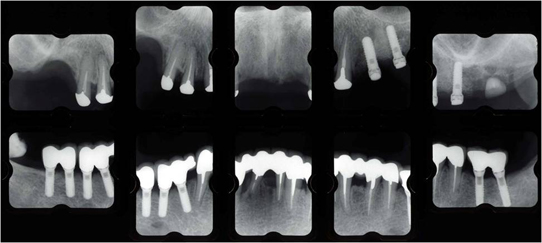

治療後

上顎は磁石義歯とし、インプラント磁石も追加し快適性を向上しました。 下顎は奥歯はインプラント治療、前歯はセラミックブリッジにて固定製にしました。

治療内容

- 磁石義歯

- インプラント磁石総義歯

- 再生治療

- インプラント(6本)

- セラミックブリッジ(8本)